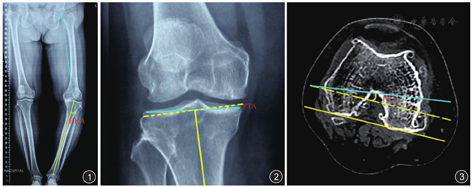

髋膝踝角(hip-knee-ankle angle,HKA)测量:在负重位下肢全长X线影像上,以股骨头中心点至股骨髁间窝中心的连线作为股骨机械轴,以胫骨髁间嵴中心与踝关节中心的连线作为胫骨机械轴,两条轴线的夹角为HKA。外翻时为正值,内翻时为负值,正常范围为0°±3°;HKA值<-3°则认为下肢存在内翻畸形,HKA值>3°则认为存在外翻畸形[10]。见图1。

PTA测量:在负重位下肢全长X线影像上,以胫骨髁间嵴中心与踝关节中心的连线作为胫骨机械轴线,从胫骨髁间嵴中心作胫骨机械轴线的垂线,内、外侧胫骨平台最低点的连线作为胫骨平台切线,从胫骨髁间嵴中心做胫骨机械轴线的垂线,该垂线与胫骨平台切线的夹角为PTA[8]。见图2。

PCA测量:在冠状面CT图片上选择内侧髁最突出的层面和外侧髁最突出的层面,以及两个层面之间的层面,在每一个层面均做股骨内外髁最高点之间的连线,以股骨内外后髁最低点的连线,两线之间的夹角为PCA,最后取每个平面测量值的平均值[11]。见图3。